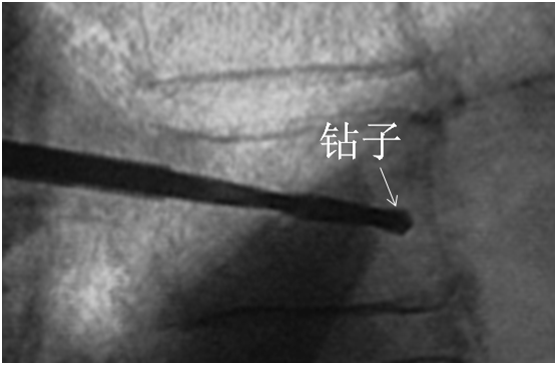

使用钻子开通道。

侧位相钻子直至椎体前中1/2交界处,正位钻头尖位于椎弓根影与棘突连线中点。

钻子必须出外鞘前端2cm,保证球囊完全进入椎体。

侧位像钻头尖在距椎体前缘2mm处停止正位显示钻头尖位于棘突边缘。